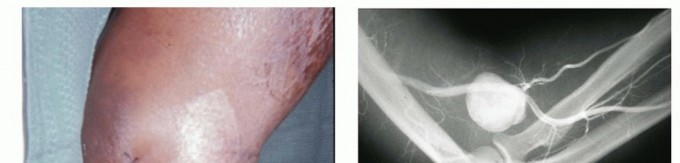

ARTERIOVENOUS MALFORMATIONS

Arteriovenous malformations have direct arteriovenous shunts without intervening capillaries and, like venous malformations, may be associated with a number of syndromes, including Parkes-Weber syndrome and Klippel-Trenaunay syndrome. These are more likely to be high flow and be complicated by ulceration and high-output failure as well as amputation (FIG 6).As with venous malformations, arteriovenous malformations may be associated with limb or digit hypertrophy.31